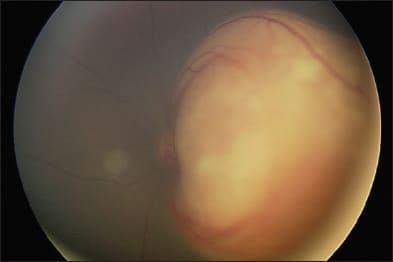

Figure 2. Left eye (left images) and right eye (right images) of a child with bilateral retinoblastoma before treatment (top images) and after bilateral intra-arterial melphalan and laser consolidation (bottom images).

For patients with bilateral disease, Abramson et al.9 also reported on the use of tandem therapy, or bilateral infusions, during the same session. In a report of four patients with advanced bilateral retinoblastoma (R-E stage V), all eyes avoided enucleation or radiation, without any serious adverse effects.